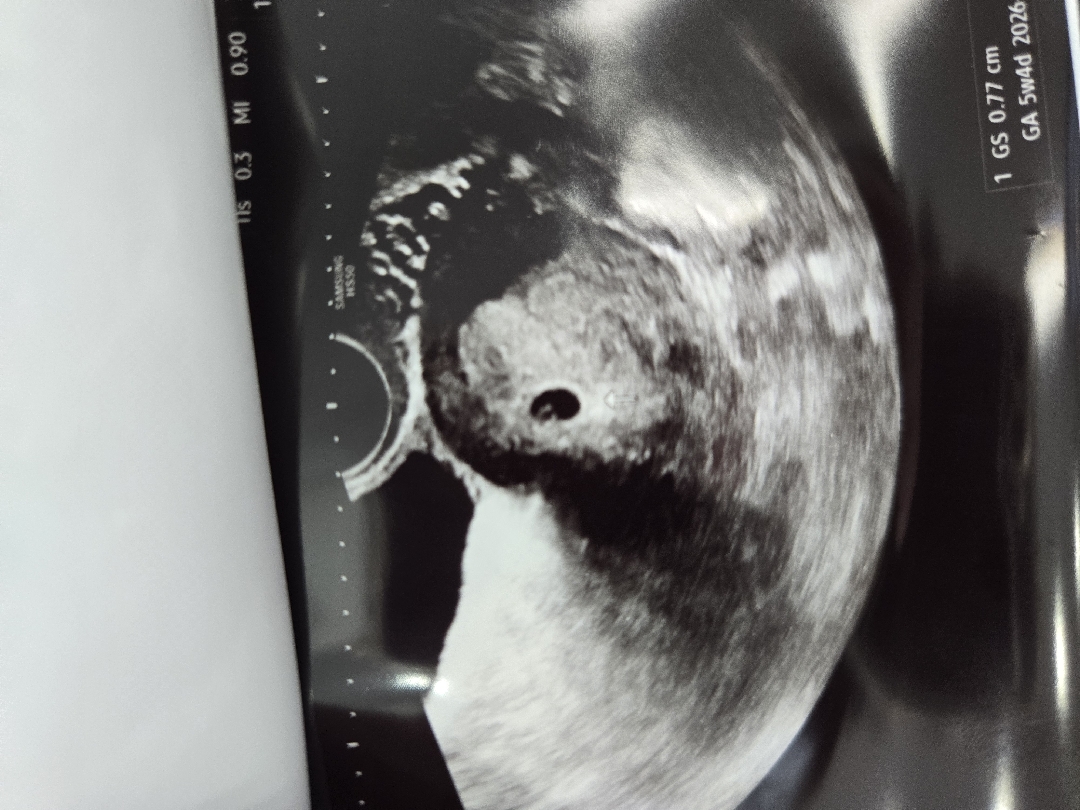

초음파 보기 전까지 걱정도 너무너무 많아서 여기에 글도 몇번 올렸는데 올릴때마다 따뜻한 답변해주셔서 초음파 보러가기전까지 많은 힘을 얻었어요ㅠㅠ... 정말 감사합니다😍드디어 오늘 아기집들이 하고 왔는데 사진엔 5주4일이라 적혀있지만 5주 2일차라 보시면 된다고 하시더라구요!! 애기집은 7.7mm 이고 애기 집 가운데 하얀 링 같은 난황 보이시나요!? 난황도 보고 왔습니다🤍 2주뒤엔 심장 소리 들을 수 있겠죠!? 아 그리고 혹시.. 당수치가 높게 나와서 그런데 티백이나 좋은 거 추천 살포시 부탁드립니다ㅜㅜㅎㅎ

너무 걱정했는데 잘 보여서 너무 기분이 좋았는데 반지같이 이쁘게 잘 만들어졌다니 또 기분이 너무 좋으네요ㅎㅎ 감사합니다아🤍